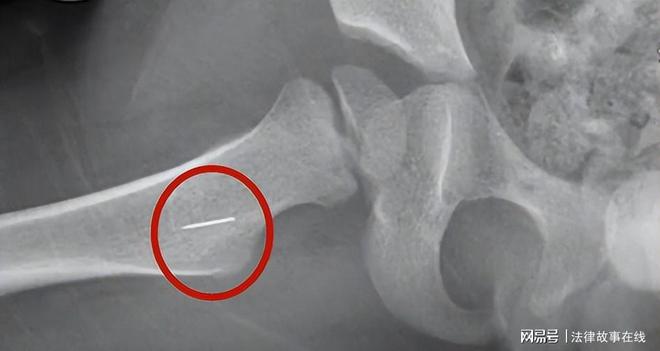

医生看过X光片诊断过后,竟然发现孩子屁股里面竟有一根针!这个结果让张先生夫妻两个感到不可思议。这根针是从哪里来的?

通过简单的手术,北京市海军总医院的医生从孩子左边屁股里面取出来一根大约长2.8厘米的断针。面对这样的结果,夫妻俩心里像被针扎了一样难受。

因为诊断发现,孩子这个右侧臀部一边深层地方还有一个异物存留,后来那个医生就怀疑,可能还是一根断针。医生建议张先生给孩子的右侧臀部也拍一个X光。

拍完后医生看成像图片,发现另外一半果然还有一根针在里面,这让张先生陷入了沉思,心一下子就凉了。

在经历了几个小时的手术之后,第二根断针终于从孩子体内被取了出来。取出来的断针是一截缝衣针,只有针尖没有针尾,全长大约有1.5厘米长。

2015年12月2日,石景山区法院开庭审理此案。庭审中,杨凯霞承认她用一根较短的针扎在小孩的右侧臀部,大约有1.1厘米左右长。

但是扎完后小孩哭闹不止,杨凯霞随即将第二根断针扎进小孩左侧臀部,大约有2.8厘米长。